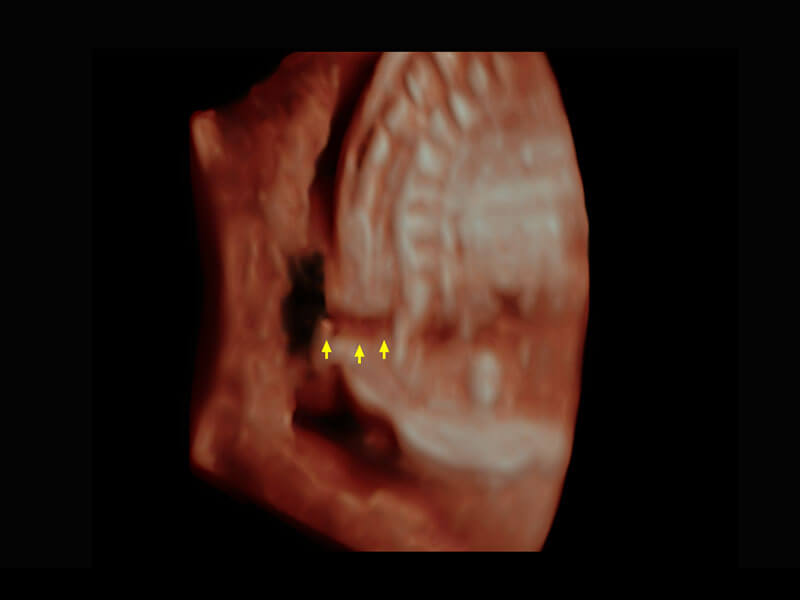

生殖健康

P60卓越的图像质量搭载专科探头,在妇科基础疾病的诊断、卵泡生长的监测、输卵管通畅情况的判别等方面为您提供全面的生殖应用方案。

• 腔内三维-宫内节育器

• 腔内三维-光影成像